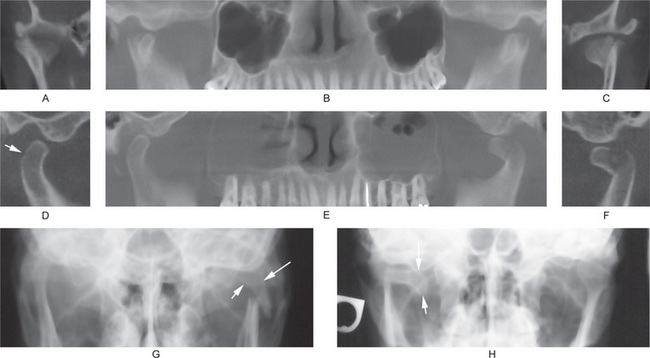

Figure 17-42 Fracture of the condylar temporomandibular joints.

(A, B, and C) From the same patient’s cone beam computed tomography scan. Both the condylar heads are vertically fractured. The reconstructed panoramic view (B) shows the fractured fragments of the condylar heads are dislocated anteriorly. (D, E, and F) From the same patient’s cone beam computed tomography scan. D, Shows a hairline fracture (arrow) of the right condylar head. Figure E shows fractured and anteriorly displaced left condylar head. Both the maxillary sinuses are cloudy. F, shows fractured left condyle, and that fracture fragment is displaced to the peak of the articular eminence. (G) Fracture of the left side at the condylar neck region. Open mouth Towne’s radiograph shows the fractured fragment (arrows) is medially inclined. (H) Fracture of the right side at the condylar neck region. Open mouth Towne’s radiograph shows the fractured fragment (arrows) is displaced medially and is horizontally oriented.